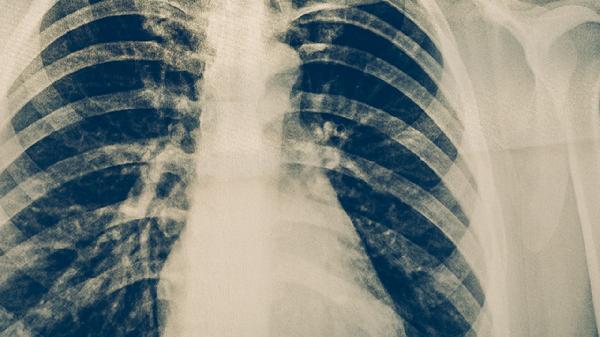

預(yù)防肺結(jié)核主要有接種卡介苗、避免接觸傳染源、增強(qiáng)免疫力、保持良好衛(wèi)生習(xí)慣、定期體檢等方法。肺結(jié)核是由結(jié)核分枝桿菌引起的慢性傳染病,主要通過(guò)呼吸道傳播,做好預(yù)防措施有助于降低感染風(fēng)險(xiǎn)。

高危人群每1-2年進(jìn)行胸部X線檢查,接觸過(guò)肺結(jié)核患者的人群需做結(jié)核菌素試驗(yàn)或γ-干擾素釋放試驗(yàn)。出現(xiàn)持續(xù)2周以上咳嗽、低熱、盜汗等癥狀時(shí),應(yīng)及時(shí)進(jìn)行痰涂片和痰培養(yǎng)檢測(cè)。醫(yī)務(wù)人員、矽肺患者等職業(yè)暴露人群應(yīng)縮短篩查間隔。